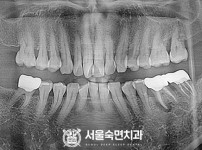

임플란트-전후사진1

임플란트-전후사진2

임플란트-전후사진3

임플란트-전후사진4